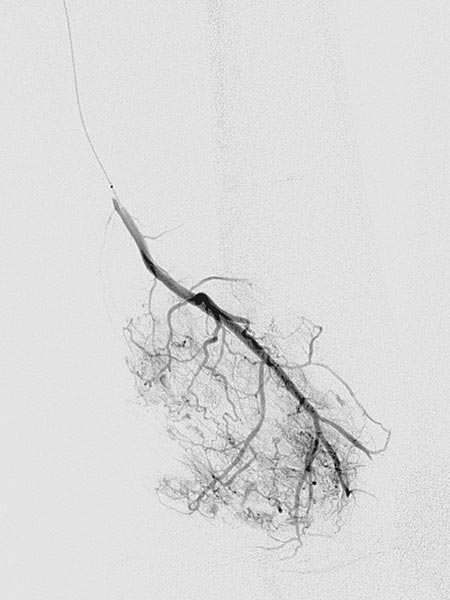

Digital subtraction angiography (DSA) in the early arterial phase shows a dilated feeding artery (so-called “feeder artery”), in this case a medial superior genicular artery. This artery is dilated over time due to chronic hyperperfusion with increased blood flow.

Digital subtraction angiography (DSA) in the arterial phase 2 s later shows some minor arteriovenous fistulas.

Digital subtraction angiography (DSA) in the interstitial and early venous phase again 4 s later shows no direct early venous outflow of the contrast agent but, instead, a pooling phenomenon. In an arteriovenous malformation, an immediate venous outflow would be seen because of multiple direct arteriovenous communications.

Super-selective catheterization of the feeding artery with a microcatheter again depicts multiple, fine arteriovenous fistulas, but not the immediate venous outflow as would be typical of an AVM. However, the visible arteriovenous fistulas are unusually prominent in this venous malformation.